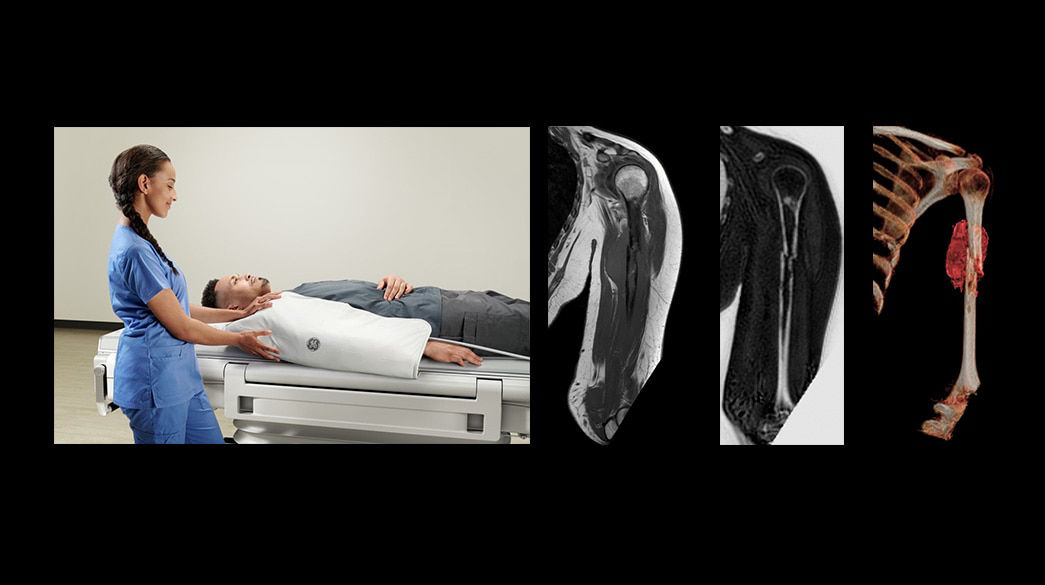

Personalized

Comfortable, acoustic reduced imaging, added to any patient